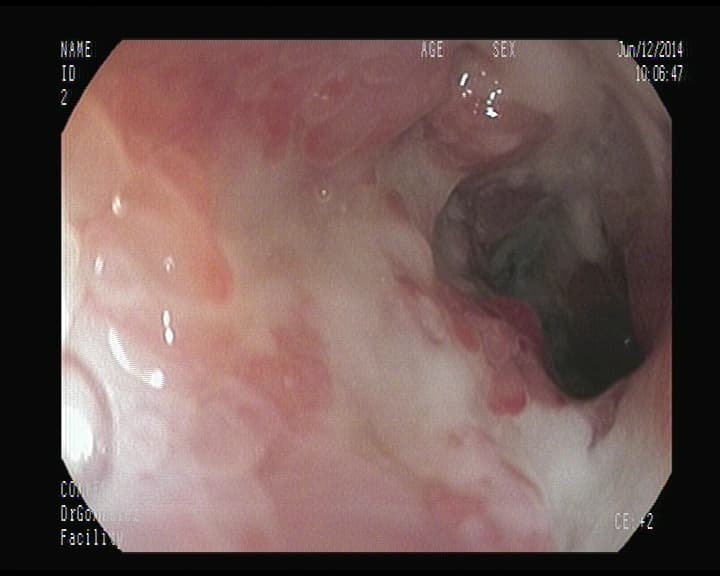

Cáncer Rectal.

Crecimiento infiltrante que afecta la mitad de la circunferencia en el extremo distal del intestino grueso- Recto-.